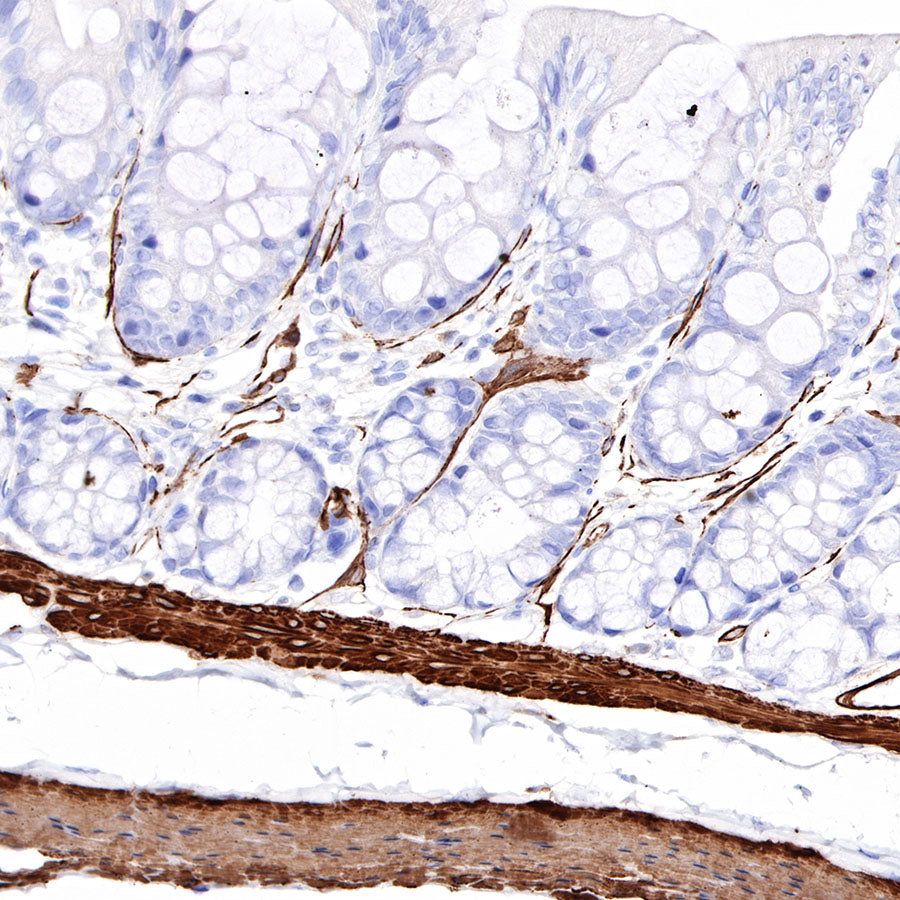

Immunohistochemistry